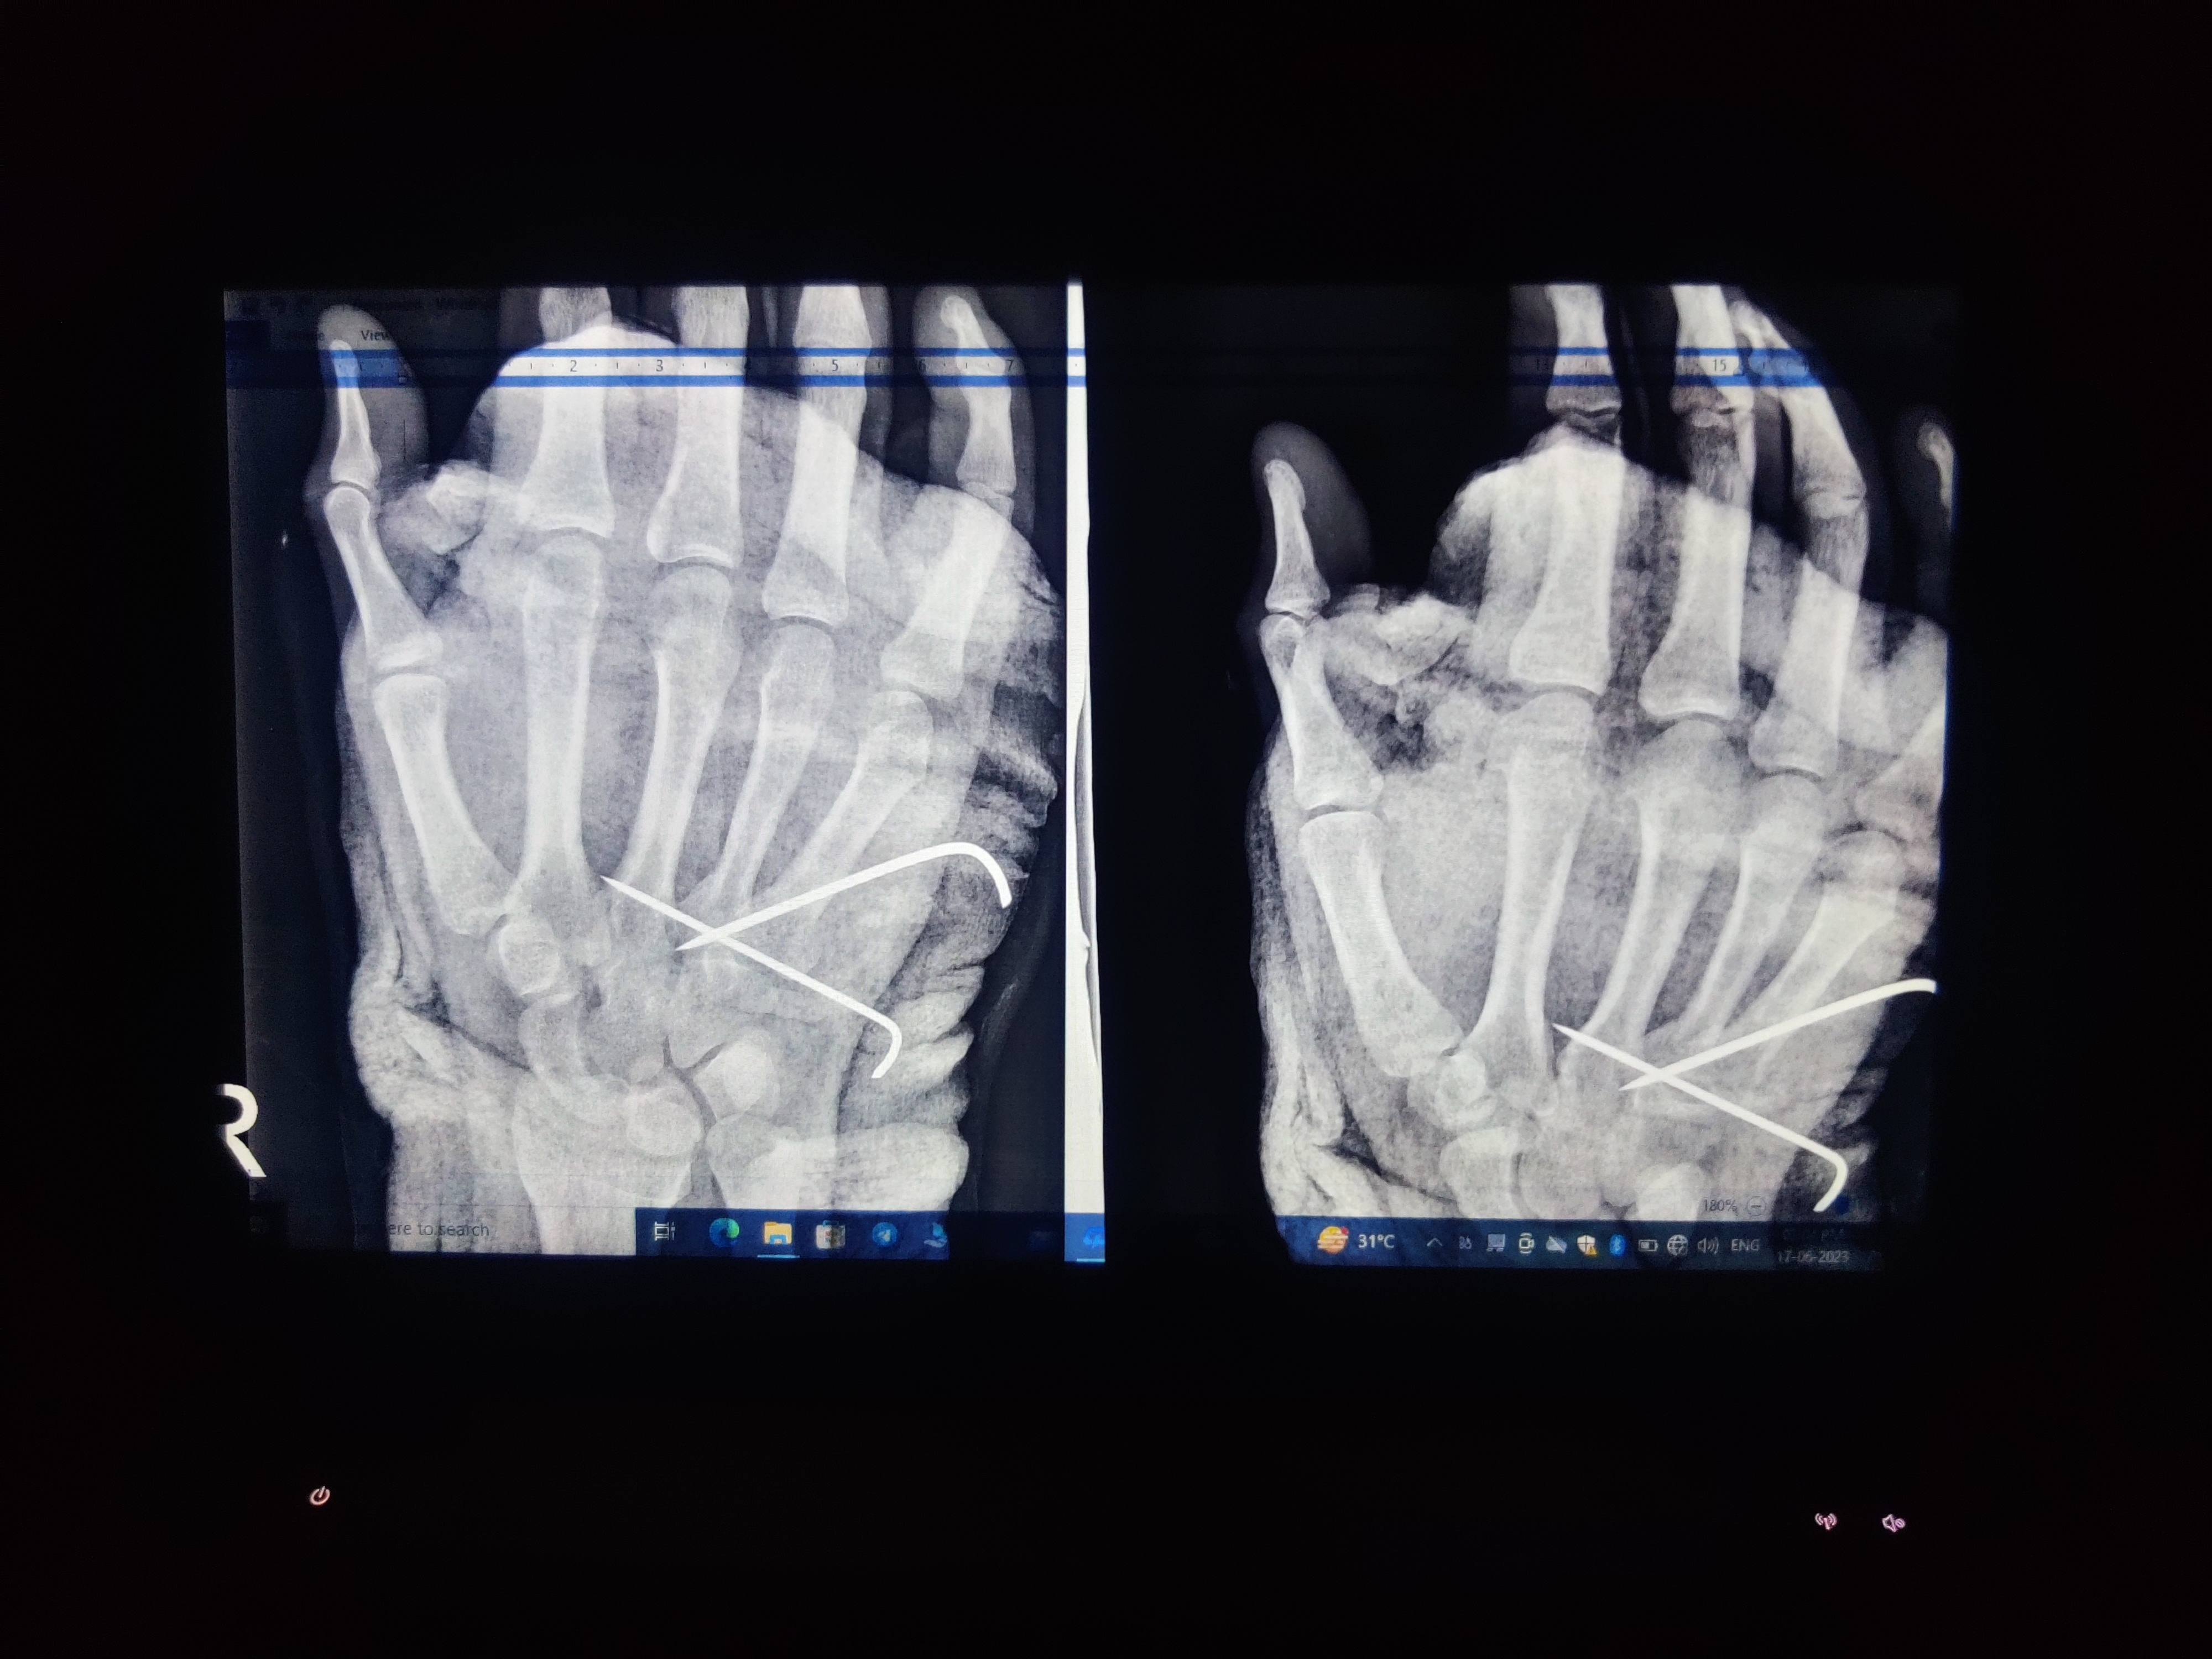

Sir i had got some fracture on hand and docs operate me on k-wire surgery on 14/06/23. Would you please suggest me for minimum how much time I'll remove those plaster and k wiring. As I have recently recruited for new job and I have to join it urgently